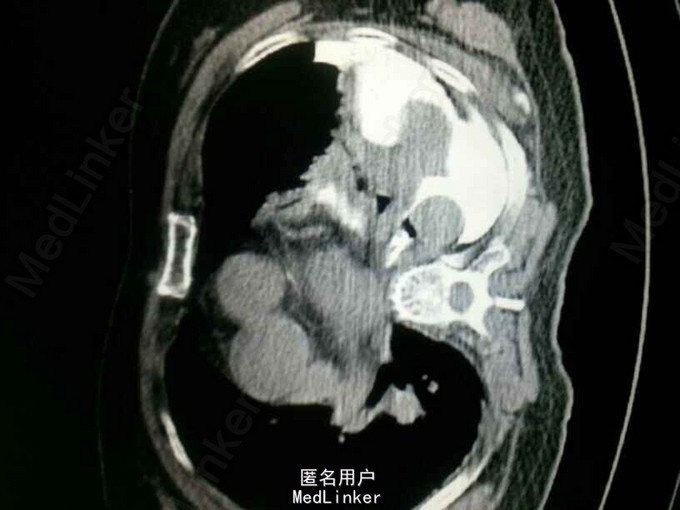

查体:气管居中,左肺呼吸音弱,右肺呼吸音尚可。未闻及湿啰音。胸腔引流管可见褐色浑浊液体引出。 腹部CT肝脾胰未见异常,胆总管扩张。 食管造影:食管下端撕裂,食管胸膜瘘。 胸CT左肺气胸,左侧胸腔内高密度影,考虑造影剂漏入胸腔。左肺实变,右侧少量胸腔积液。

诊断:自发性食管破裂。 治疗:急诊行胸腔闭式引流。后行左剖胸食管破裂修补。术中见胸腔污染严重,见菜叶,消化液等。后纵膈可见较多脓性分泌物,食物残渣,坏死组织。食管裂口处上方可见5cm纵向肌层及粘膜层撕裂口,相应位置处可见纵膈胸膜撕裂口。术后予肠内肠外营养,舒普深,泰能,稳可信,抗感染,术后反复行2次食管造影,仍存在食管破裂口,术后一月行胃镜及食管支架植入术。第二天行进食流质及半流质通畅,平稳出院。